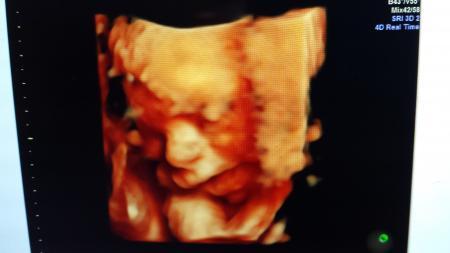

... war schön :-) Den kleinen so in 3 bzw 4 D zu sehen ist schon was anderes... Er ist immer noch sehr zart, bei 26+3 777g, aber er hat etwas zugenommen und liegt auf der untersten Perzentile. Da mein Gyn ein Spezi in Ultraschall usw ist, hat er nen Doppler und alles gleich mitgemacht . Alles gut soweit. Puh..m

Foto anbei